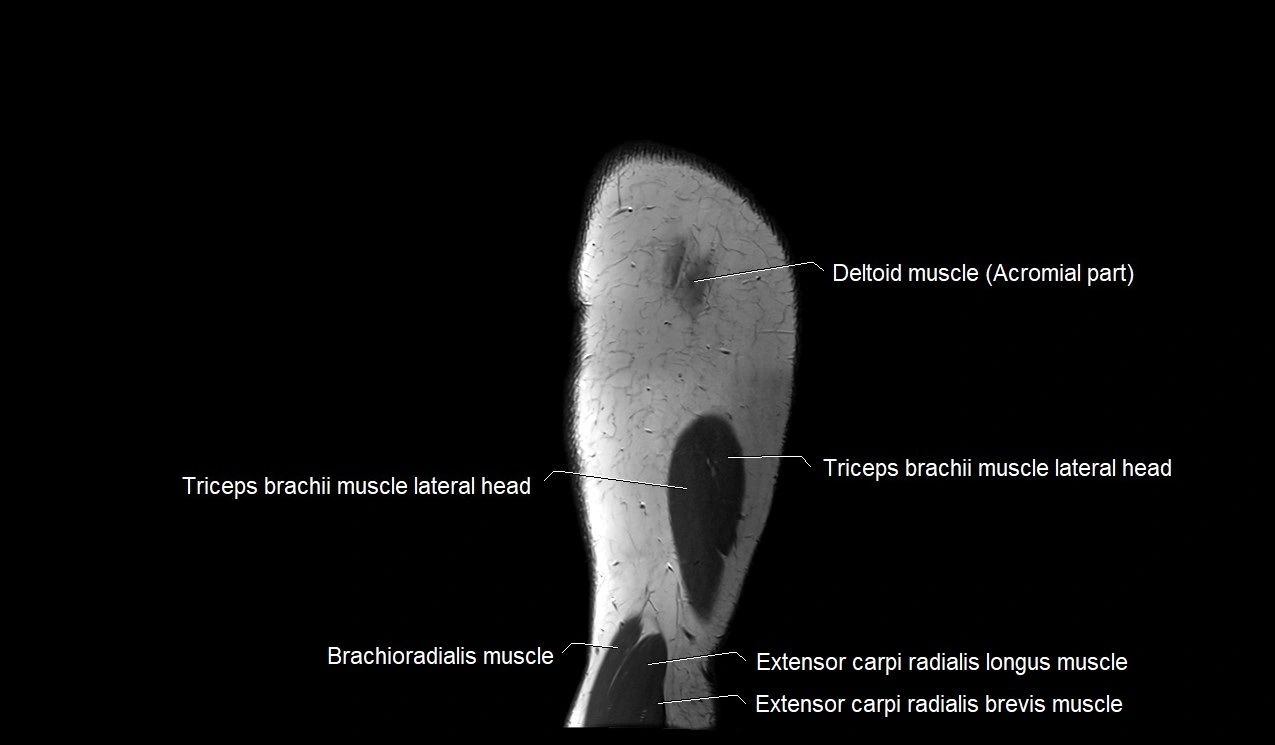

- Brachioradialis muscle

- Extensor carpi radialis brevis muscle

- Extensor carpi radialis longus muscle

- Lateral head of triceps brachii muscle